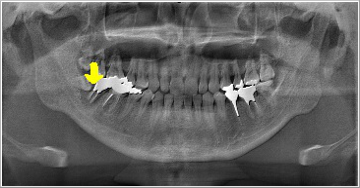

これは横向きに出てきた親知らずとその前の歯との間に食べ物が詰まり、取れなくなった為に奥の方まで炎症が広がり、結果的に前の歯を抜かなければならなくなった症例です。 この患者さんは「右下奥歯が動き出し、痛くて噛めなくなりました」といって来院されました。

親知らずは虫歯にならず、その前の歯だけに大きな虫歯を造っている親知らずもあります。

また、一見それほど大きな虫歯ではない様に見える歯でも、少し顔を出した親知らずの為に抜かなければならぬ程の大きな虫歯になっている事もあるのです。